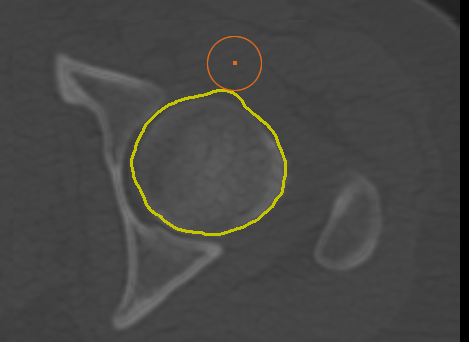

Adds a new path in Snap mode to the current group of paths. You use the Snap tool to create a path by simply dragging inside a feature on a 2D view. The contour line will automatically snap to the gradient that defines the edges of the targeted feature. Do the following to draw a path in Snap mode: